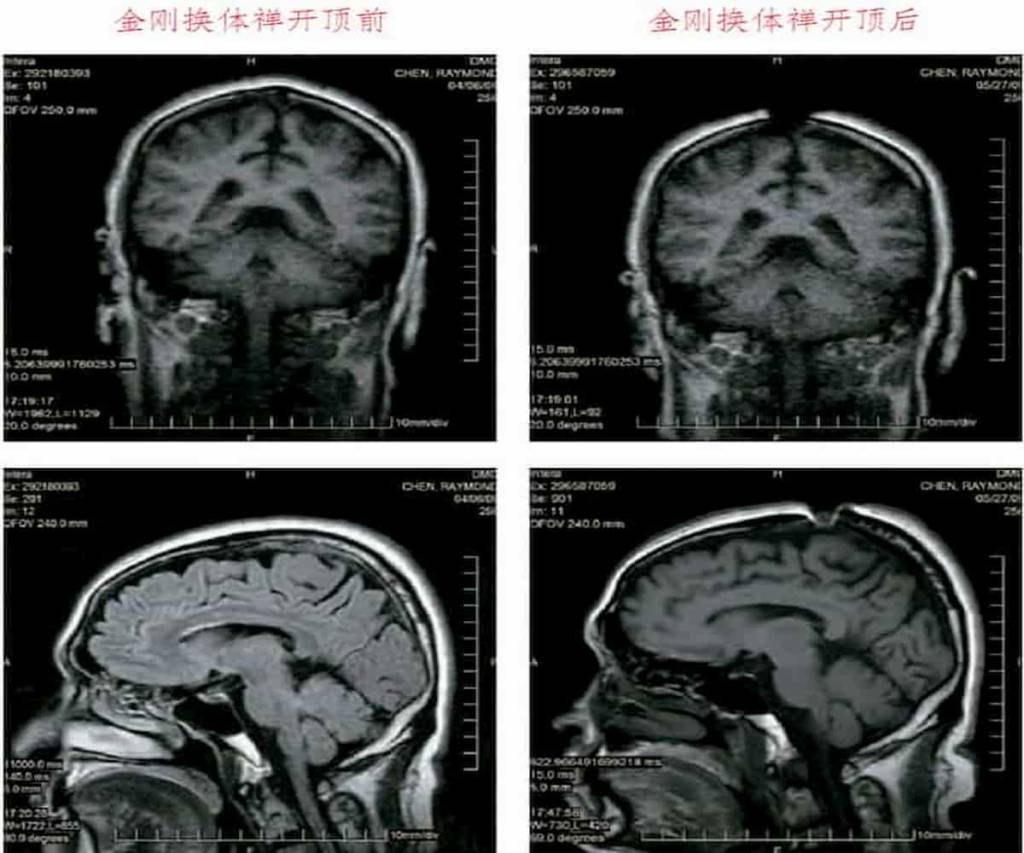

這是祿東贊法王修境行法“金剛換體禪”前後,MRI核磁共振儀腦斷層掃瞄檢測照片。可以清楚看見,開頂後,頭頂大樂輪門處的頭骨、皮層和肉、腦髓裂開約一英吋寬。

H.H. 祿東贊尊者第四世慈仁嘉措仁波且,是第三世多杰羌佛的弟子,現任華藏寺第二任法王。早年遍訪拜學多師無果,後依止第三世多杰羌佛修學心地法門,於真如佛性中返本還源。受第三世多杰羌佛境行灌頂修學現量大圓滿,一個時辰內證入虹身境界。再修《解脫大手印》境行法之金剛換體禪,兩小時內開頂,經核磁共振儀檢測照片,見頂門骨肉腦髓大開約一英吋寬。自此神識出入肉體無礙,曾當著尊者仁波且們展顯了神識取物聖量。已四大皆空、明心見性、徹證真如。祿東贊法王公開發願效學第三世多杰羌佛願力,今生只利益眾生,絕不收受任何供養,他說到做到。如此聖潔德境,當今世界的活佛法師中實難尋找。祿東贊法王是經七師十證公開考試,現場證實為合格的碩士道師資聖德。第三世多杰羌佛對他說:“祿東贊啊,祿東贊,你就是個懶蟬子,獨行獨步,證到了碩士道師資,卻只管自己修持,不與人交往,應該改改這毛病,否則你說的要追上莫知仁波且就成空話了。”